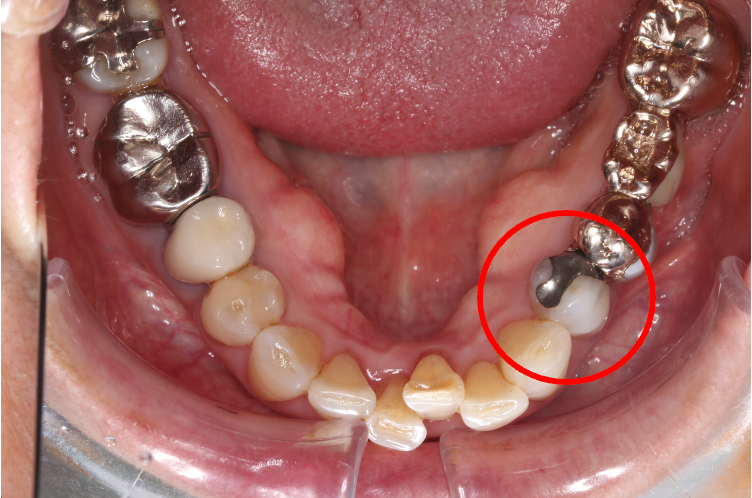

セラミック症例②

年齢 40代女性

治療期間 1ヶ月

治療内容 ジルコニア

治療箇所 右上6番

治療費用 100,000円